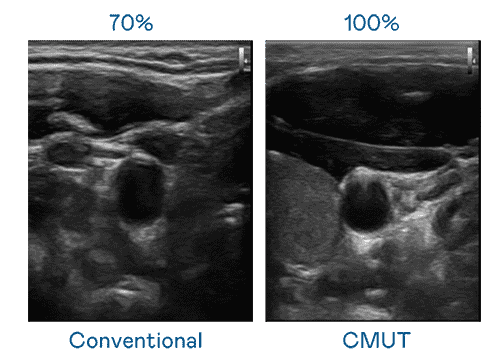

CMUT 技术是一种用电容式微机电元件来产生超音波讯号的技术。。。与传统 PZT 压电式技术相比,,,,CMUT 频宽增加 30%,,更宽频的超音波讯号让影像解析度大幅提升,,是实现高影像品质医疗超音波扫描、、、、促进精准医疗发展的关键技术。。。

超音波影像的解析度高低,,,首先取决于探头能发出的讯号频宽。。银河集团 CMUT 可提供高清晰的超音波讯号,,,,提供高频宽、、、高灵敏度、、、、影像纹理细节更高的超音波影像,,,协助医护人员缩短影像判读时间及利用精准的医疗影像进行诊断。。。。